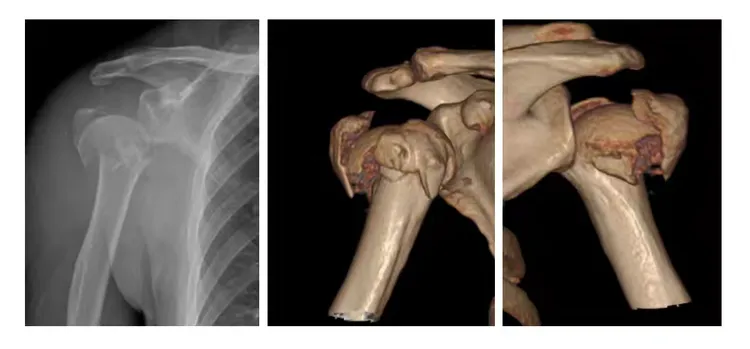

↑术前患者右肩影像学资料:左图(右肩正位片)中图(右肩CT骨三维重建前面观)右图(右肩CT骨三维重建后面观)

60岁的邓先生因意外摔伤导致右肩部剧烈疼痛、活动完全受限,经CT检查确诊为右侧肱骨外科颈粉碎性骨折伴肩关节脱位、肱骨头向后外侧90度翻转,周围软组织严重肿胀,伤情危急。更棘手的是,邓先生既往有双侧人工全髋关节置换手术史12年,传统手术方式均难以适配其复杂伤情。我院创伤中心陈仕雄主任表示,患者病情精准契合反式肩关节置换术适应症,该技术是复杂肩关节终末期病变的“终极诊疗方案”。